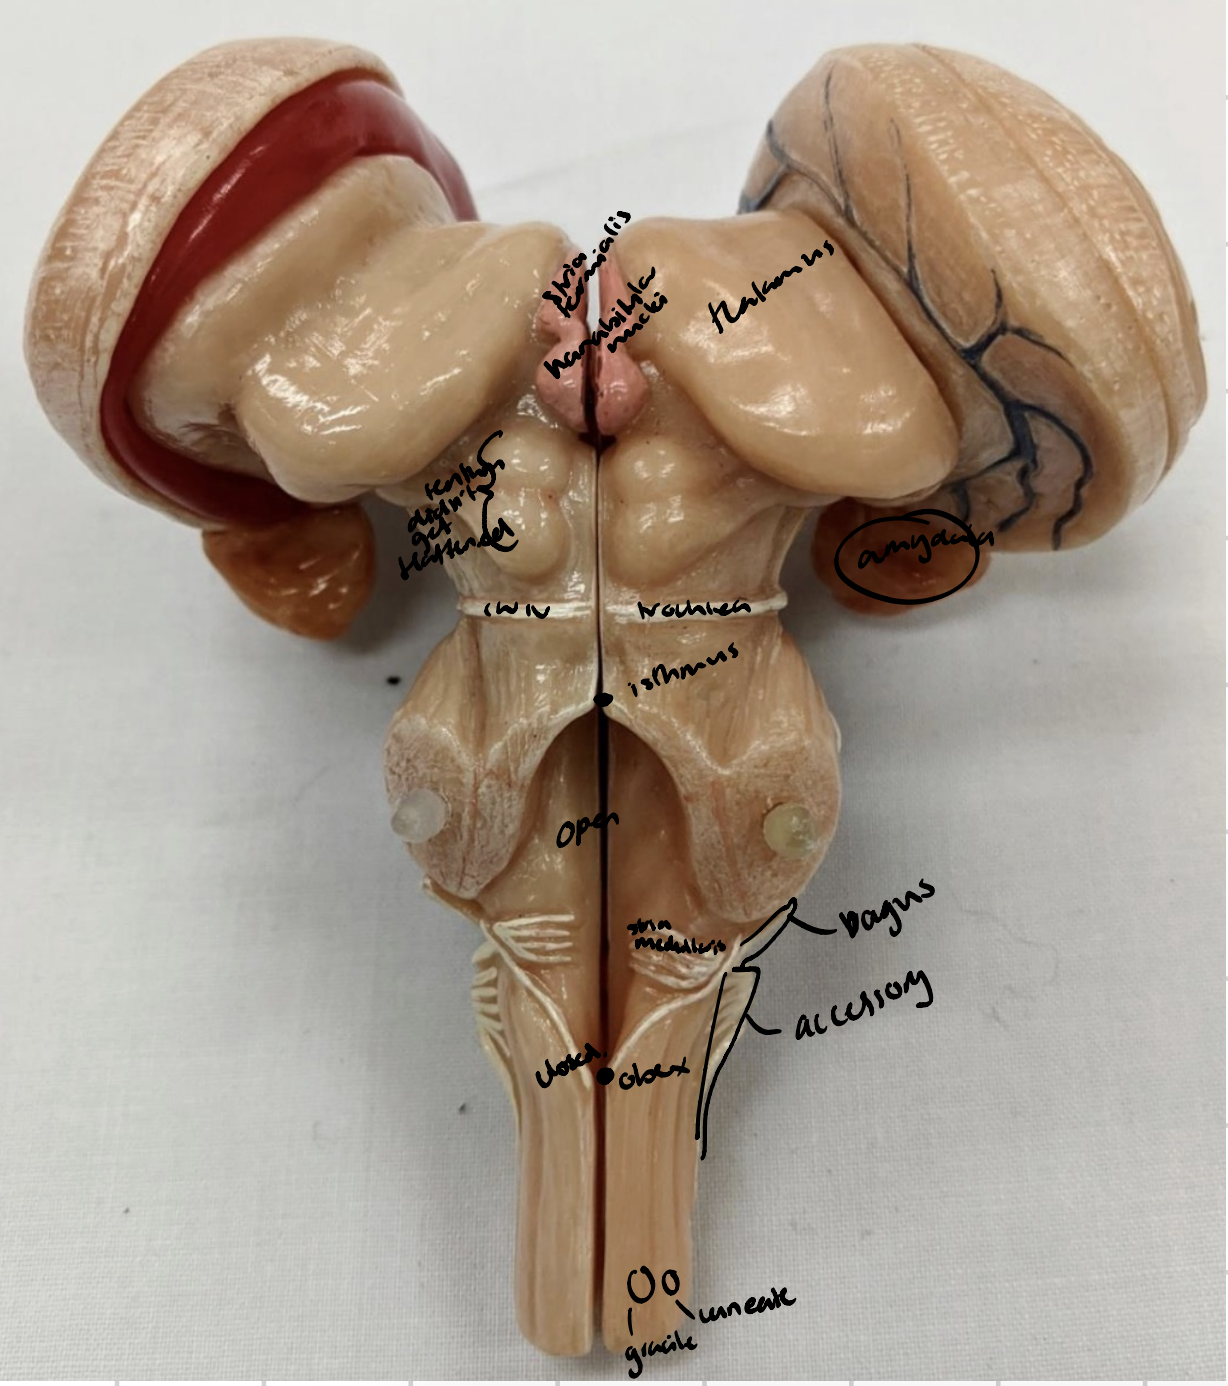

Anterior median fissure

Posterior median sulcus

Posterolateral

Anterolateral sulci

Diencepathon

Thalamus

Interthalamic mass

Striae medullaris thalami

Habenular nucleus

Pineal gland

Hypothalamus

Cerebellum

Anterior lobe of cerebellum

Horizontal fissure

Posterior lobe of cerebellum

Cerebellar tonsils

Posterolateral fissure

Superior medullary velum

Arbor vitae

Folia

Amygdala

Mammillary bodies